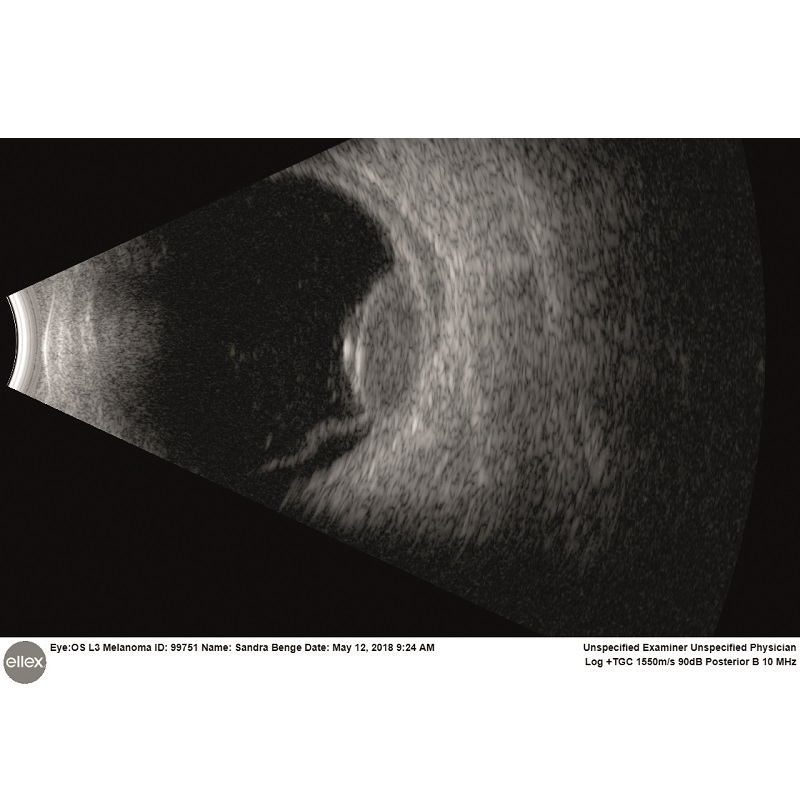

Intuicyjna platforma ultrasonograficzna Eye One obejmuje szeroki zakres trybów skanowania zarówno w odcinku tylnym, jak i przednim. Sprzęt jest w stanie wykryć najsubtelniejsze echa ciała szklistego, oferując niezwykłą dokładność diagnozy siatkówki, naczyniówki czy twardówki. W przednim trybie szerokiego pola Eye One umożliwia oglądanie całego segmentu oka w celu zidentyfikowania przyczyn choroby związanej z jaskrą oraz dokładnego i spójnego pomiaru kluczowych parametrów kąta.